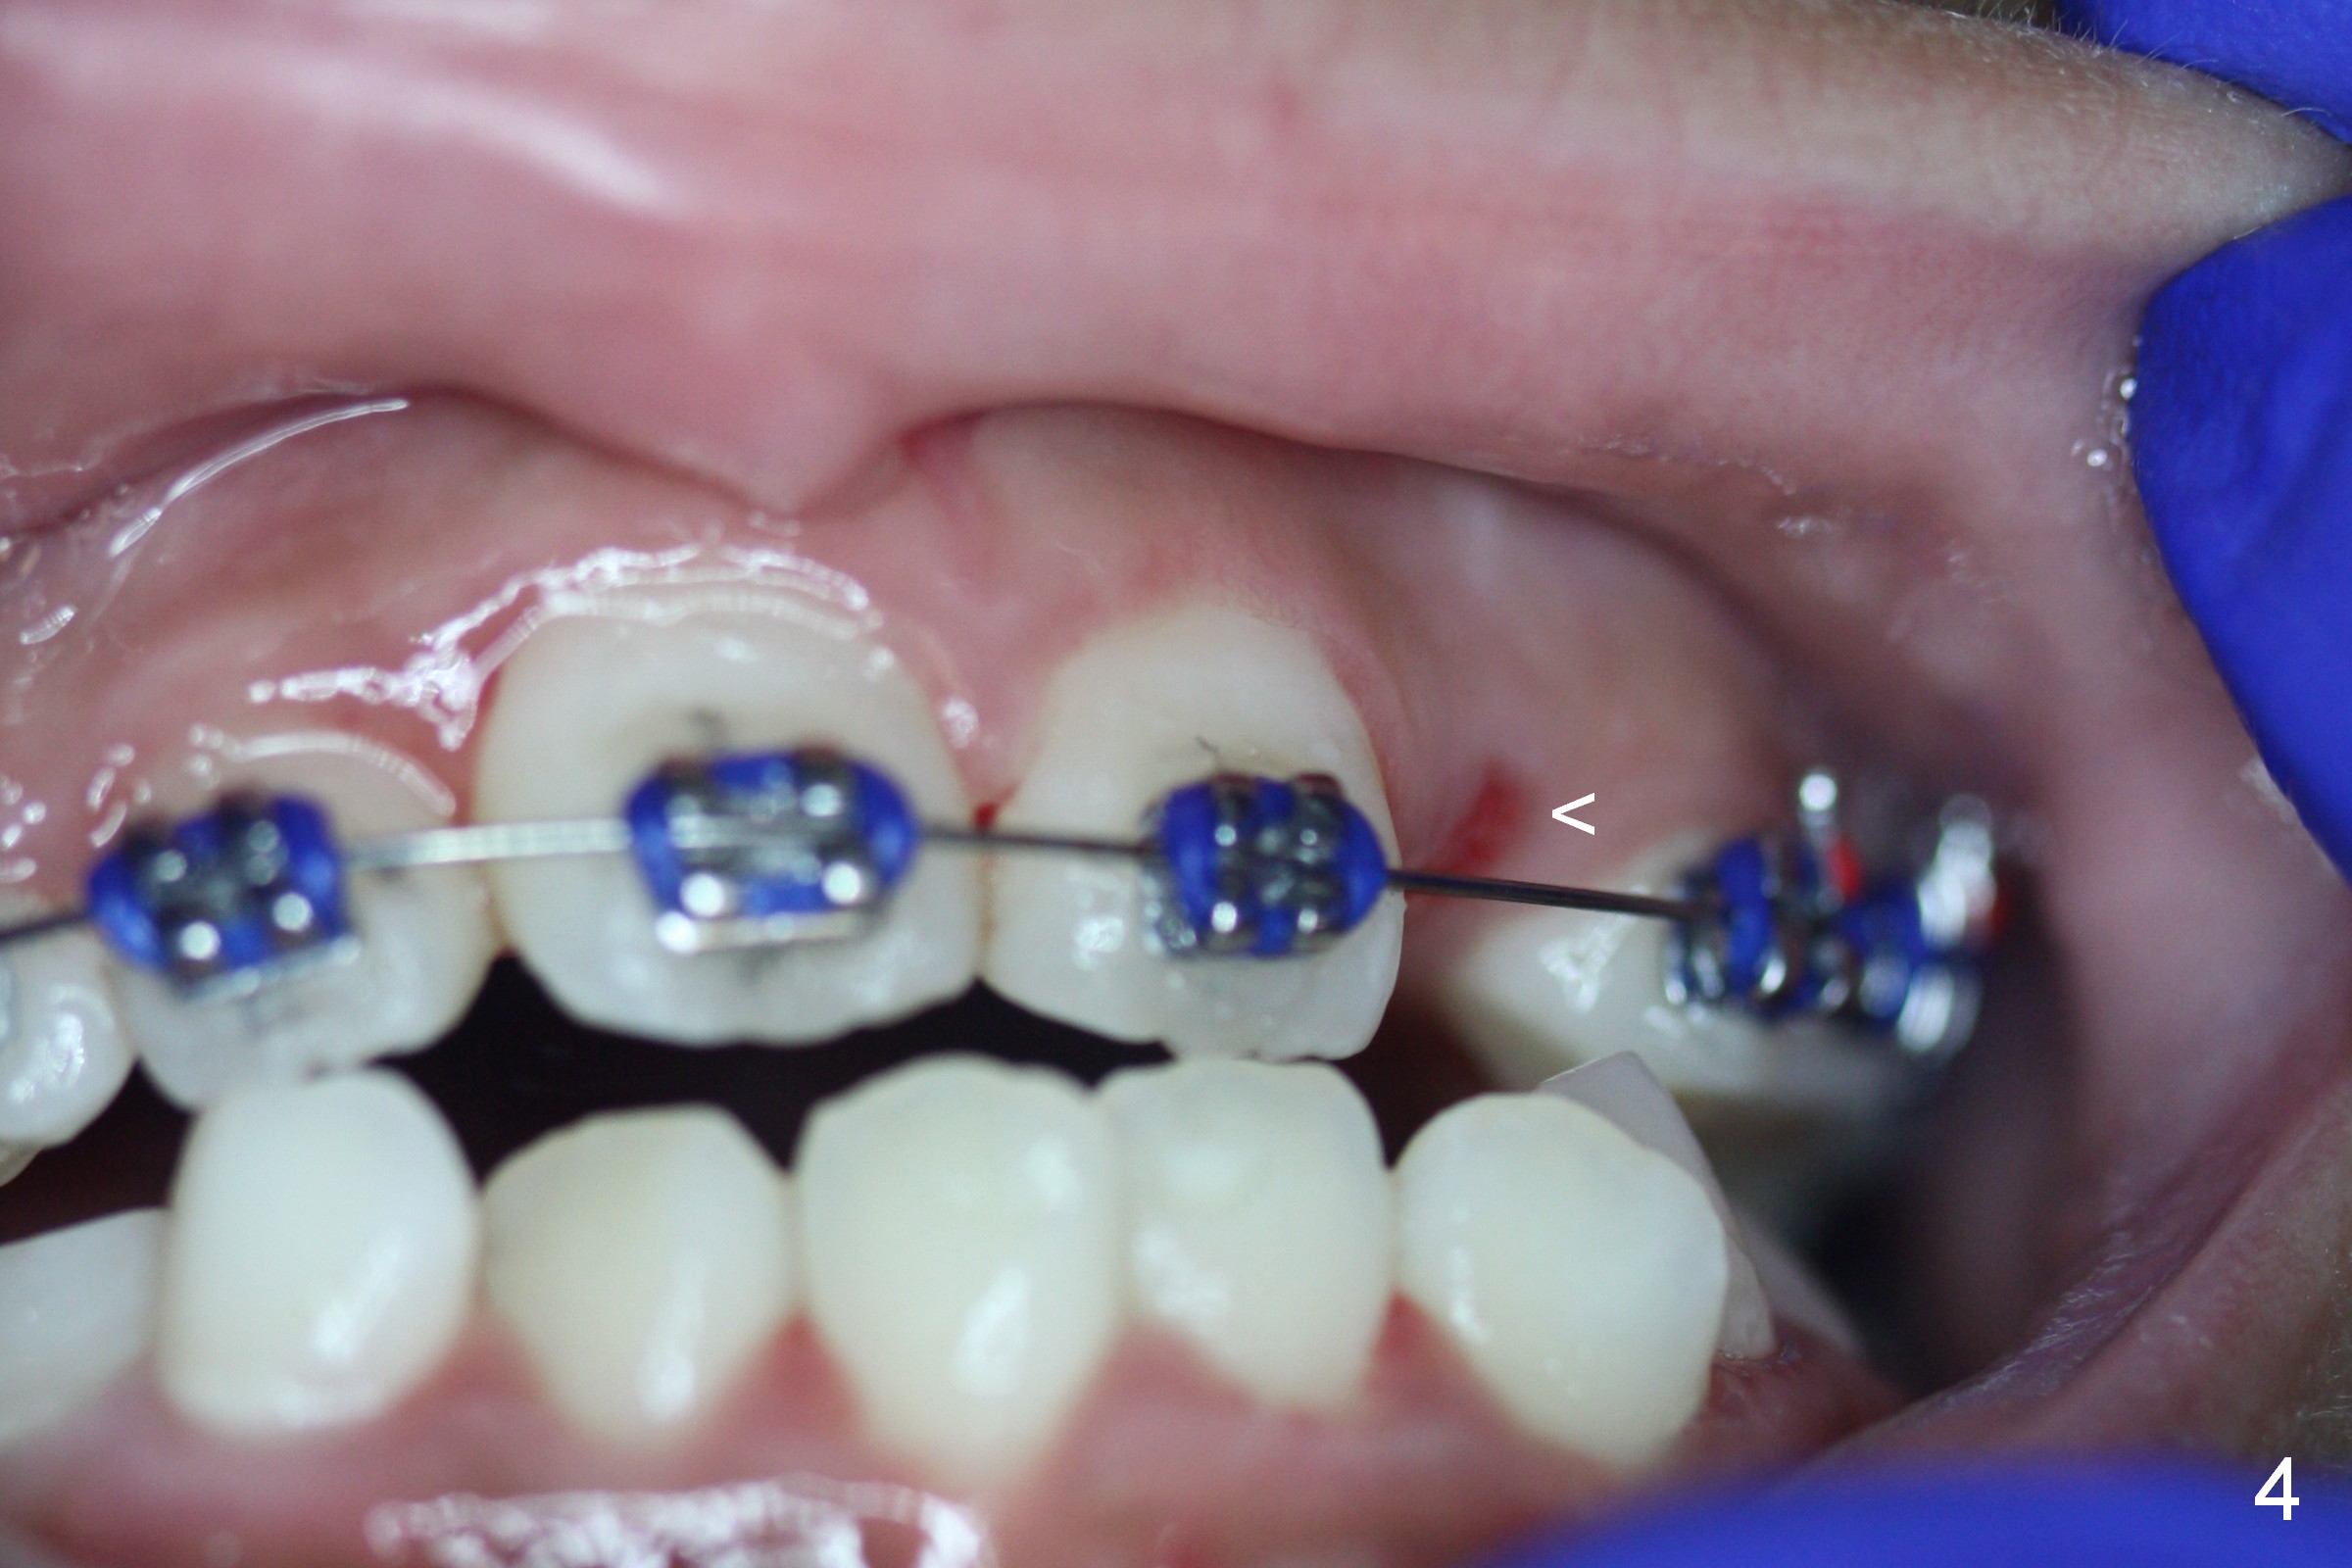

Three weeks later, the cross bite is partially corrected (Fig.4).